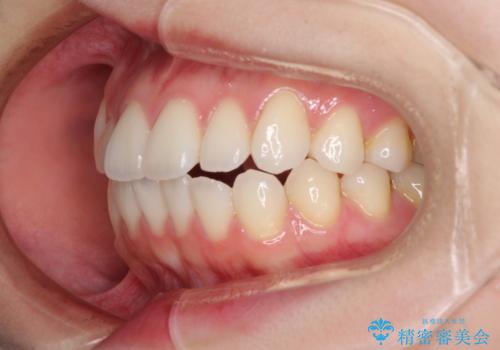

- 矯正治療の後戻りを気にして来院された患者様です。

後戻りは軽微でしたが、舌突出癖が認められ、初診時には上下前歯に舌がはまるスペースができていました。

舌突出癖の改善を行いながら、インビザライン・ライトにより矯正治療を行うこととしました。

舌突出癖の改善により上下前歯が接触するようになり、前歯でものを咬みきる必要のある食事がスムーズに行えるようになりました。